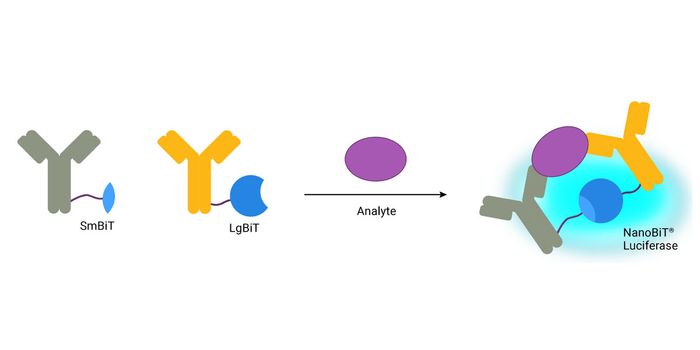

JUN 20, 2016Clinical & Molecular DXA new way to detect antibodies in blood opens the door to developing simple diagnostic tests for diseases for which ...